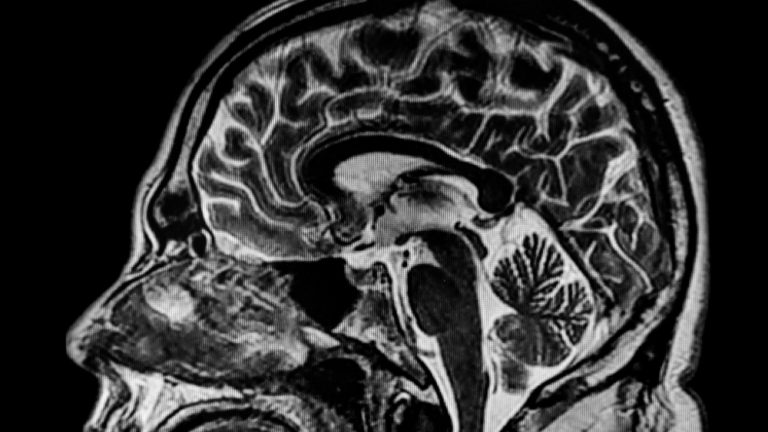

To, že člověk cítí blízkou smrt, potvrzuje mozková aktivita v posledních momentech

V posledních momentech života zažijí mozky umírajících pacientů obrovský vzestup aktivity v oblastech tzv. hotspotů. To naznačuje výskyt zkušenosti blízké smrti.

Sbíhání oblastí v mozku

Mozek se výrazně projevil v tzv. hot zone, která je silně spojena s vědomými aktivitami. Právě tam se sbíhá spánkový, temenní a týlní lalok. Prudký nárůst činnosti v těchto místech se na konci života dá vysvětlit zkušeností blízké smrti. Tu často popisují lidé, kteří se dostali skutečně až na práh této hranice, případně strávili nějakou dobu i za ní. Fenomén NDE (near death experience) popisuje 10–20 % lidí, kteří přežili infarkt. I průběh bývá podobný.